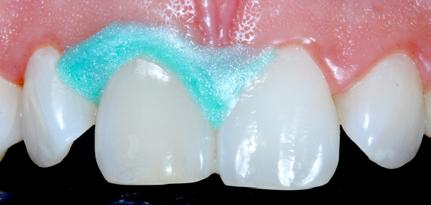

• Selective etching of the enamel is recommended.

• Use XBW shade of G-aenial® Universal Injectable for easy differentiation between the tooth, composite material and the restoration.

3. Etch the enamel.

4. Apply a bonding agent (G-Premio BOND or G2-BOND Universal).